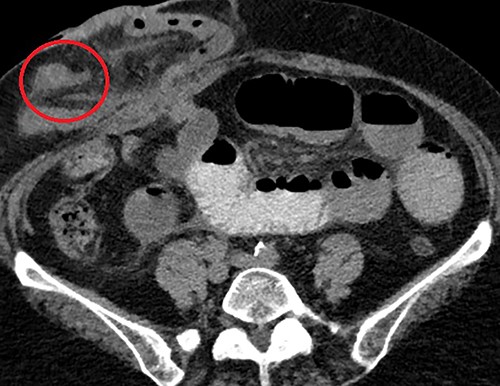

Clinical presentation of this diverticulum, if not asymptomatic, is gastrointestinal bleeding, bowel obstruction or inflammation/perforation [2]. Attempting to diagnose MD using CT imaging in patients with generic symptoms of abdominal pain or bleeding has an impressively low yield – often indistinguishable from adjacent loops of small bowel – thus a majority in adult patients are detected incidentally during surgery [3]. In the present case, after confirming the finding operatively, a close retrospective review of the CT identified the diverticulum (Fig. 2).

Axial CT scan demonstrating the MD (circled) arising from the anti-mesenteric aspect of the ileum within the parastomal hernia, identified after close retrospective review of imaging post operatively.